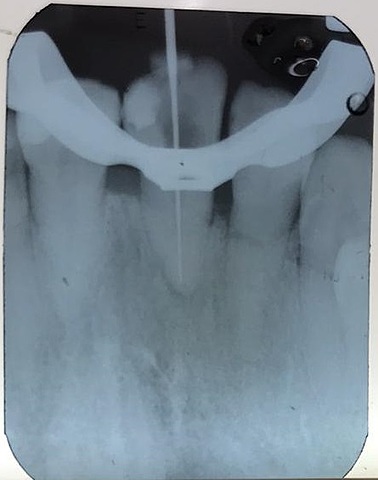

Se realizó inicio de tratamiento endodóntico en OD 1.1 se tomo cabometria, se instrumento hasta lima # 50, se realizó el retroceso con limas # 60, 70 y 80, se coloco hidróxido de calcio en el conducto y se obturó de manera provisional con CAVIT

Se retiró el material de curación, se colocó una gutapercha numero 50 y tres accesorias FM con SIELAPEX y se obturó de manera provisional con CAVIT